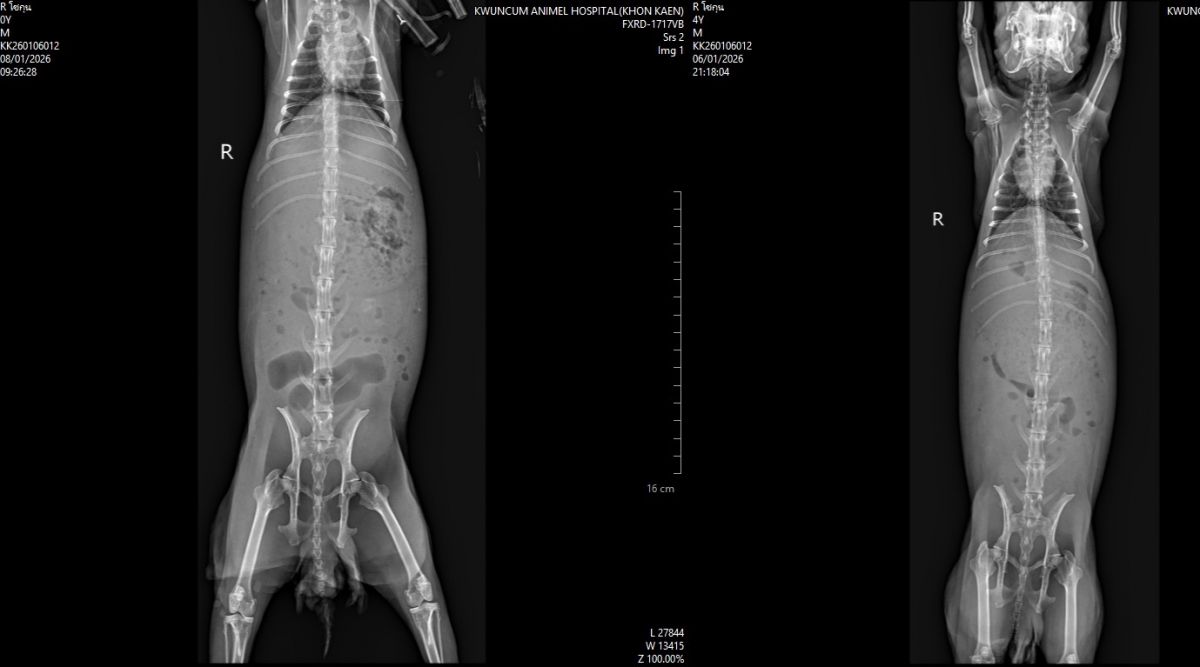

Recently, Shogun suddenly became ill, showing symptoms such as loss of appetite, difficulty passing stool, and signs of pain. After veterinary examination, he was diagnosed with liver torsion, a life-threatening emergency condition in rabbits that requires urgent surgery by a specialist. Without timely treatment, his life is at serious risk.

Surgery to treat Shogun’s liver torsion Medication and post-operative care Additional medical examinations and treatments as advised by the veterinarian